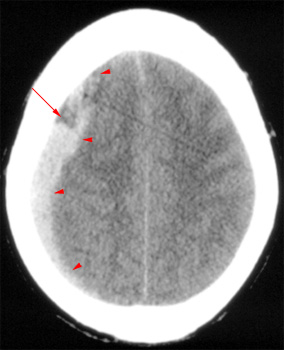

Question 8: Which of the following is NOT shown in this CT?